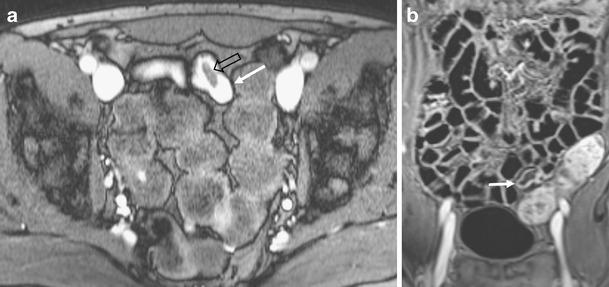

We present a spectrum of less common and less well-known bowel and mesenteric diseases (e.g. internal hernia, intussusception, neuroendocrine tumour) from our small bowel MR database of over 2,000 cases.

These diseases can be found in patients referred for bowel obstruction, abdominal pain or rectal blood loss. Further, in patients with (or suspected to have) Crohn's disease, some of these diseases (e.g. neuroendocrine tumour, familial Mediterranean fever) may mislead radiologists to erroneously diagnose active Crohn's disease.

我们从 2000 多例小肠 MR 数据库中展示了一系列不太常见和不太知名的肠道和肠系膜疾病(如内疝、肠套叠、神经内分泌肿瘤)。

这些疾病可发生于因肠梗阻、腹痛或直肠出血而就诊的患者中。此外,在(或疑似患有)克罗恩病的患者中,这些疾病中的一些(如神经内分泌肿瘤、家族性地中海热)可能会误导放射科医生错误地诊断为活动性克罗恩病。